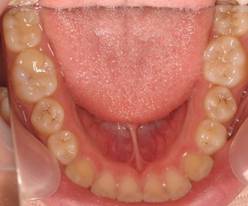

インビザGOによる矯正症例1 16歳男性

マウスピース矯正開始前。右上犬歯が内側にありました

4か月後。犬歯が外側に出てきました

治療終了後10か月